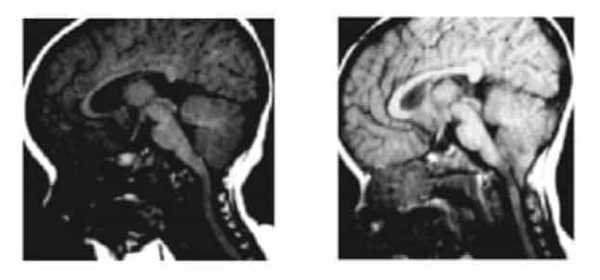

Рисунок 2.- МРТ пациента в 8 и 20 месяцев, на втором снимке можно наблюдать опущение миндалин мозжечка, которое появилось уже после первого МРТ. Huang P. “Adquired” Chiari I malformation. J. Neurosurg 1994. Это указывает на то, что, помимо наследственного и генетического фактора, существует фактор приобретенного заболевания.